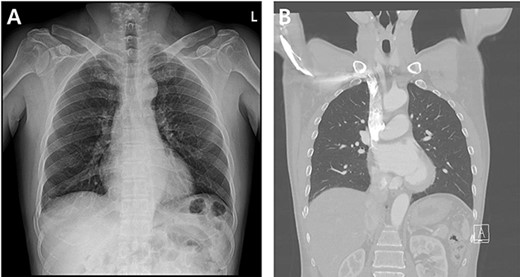

A 59-year-old man was admitted with multiple rib fractures and liver contusion due to a fall injury. He was standing on a chair for working at a farm, and it was knocked over causing him to fall and hit his flank against the corner of the chair. There was continuous pain while resting at the right flank and severe pain with pressure was noted, but no external wounds or bruises were observed. There were right 7th–11th rib fractures, scanty pneumothorax, minimal hemothorax and a 2-cm-sized liver contusion in abdomen and chest computed tomography (CT) scan (Fig. 1A, B). He was hospitalized for pain control and close observation in the general ward, and conservative management was initiated. Also, no significant changes were noted in the following daily follow-up chest radiographs. The patient suddenly complained of right-sided chest and back pain aggravation, cold sweating and fatigue 80 h after the traumatic injury. His mental status was alert, but v/s including systolic blood pressure (SBP) of 100–120 mmHg, heart rate (HR) of 40-60 beats/min and oxygen saturation of 100% during the admission changed to an SBP of 86/60 mmHg, HR of 88 beats/min and oxygen saturation of 97% when the symptoms occurred. Chest radiography was performed after the patient experienced aggravated symptoms, such as right-sided flank pain, cold sweating and fatigue. Compared to the previous scans, signs of increased opacification and peribronchial and parenchymal infiltrations were observed, which were indicative of hemothorax (Fig. 2A, B). We performed enhanced dynamic chest CT to identify any presence of active bleeding. On the chest CT scan, a large amount of hemothorax was identified in the right lung field along with multiple fractures of the right ribs. However, there were no signs of contrast leakage indicative of active bleeding (Fig. 3). Hemoglobin levels decreased from 13.1 g/dl on the day before the symptoms appeared to 11.5 g/dl at the onset of symptoms and to 9.4 g/dl after 2 h. Four packs of RBC transfusion and fluid were administered to the patient, and he was moved to the intensive care unit for close monitoring. And tube thoracostomy was performed, and 1600 ml of fresh blood was drained (Fig. 4A). The following day, 500 ml of blood was drained through the chest tube, but his v/s were stable (Fig. 4B). The amount of bleeding through the chest tube was decreased, but the drained fluid was fresh blood. And we thought that the remaining hematoma was not effectively drained, so the patient’s respiratory discomfort could persist and cause uneffective ventilation. And then we consulted with the Department of Thoracic Surgery, and video-assisted thoracoscopic surgery (VATS) exploratory thoracotomy was performed to identify the bleeding source caused by displaced rib and evacuate the large amount of hematoma. There was a large volume of hematoma within the pleural space and between the right lower lobe, diaphragm and fissure, but no active bleeding point was located. The fractured right 10th rib pierced through the pleural space and was displaced to the thoracic cavity, which was easily reduced. There was no injury surrounding the diaphragm, and although the general lung and chest wall contusions were severe, there were no signs of lung parenchymal lacerations (Fig. 5A–C). Chest tube drainage was serous, and there was no further bleeding. There were no signs of bleeding or any other abnormal findings on chest CT performed at the outpatient clinic, and the patient had no complaints of any symptoms (Fig. 6A, B).

Radiographic findings. (A) Day of symptoms, chest X-ray in the morning. (B) Chest X-ray after symptoms develop.